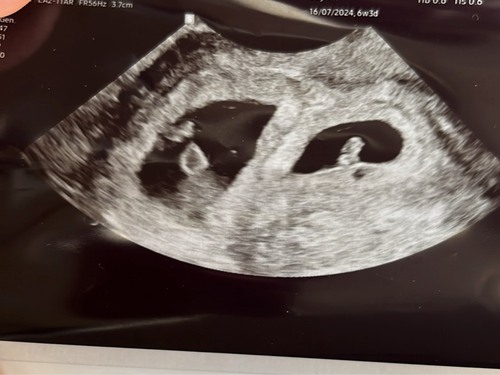

Vandaag eerste echo op 7 weekjes gehad en tot mijn verrassing 2 ❤❤ 🥰🥰

Dit is mijn echo vndg